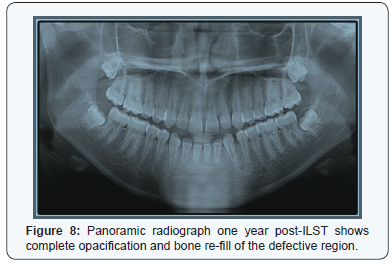

One year later, there was no mobility of the teeth No. 33 & 34, reduced size of bony swelling (Figure 7) and panoramic radiograph has shown complete re-ossification of the region (Figure 8).